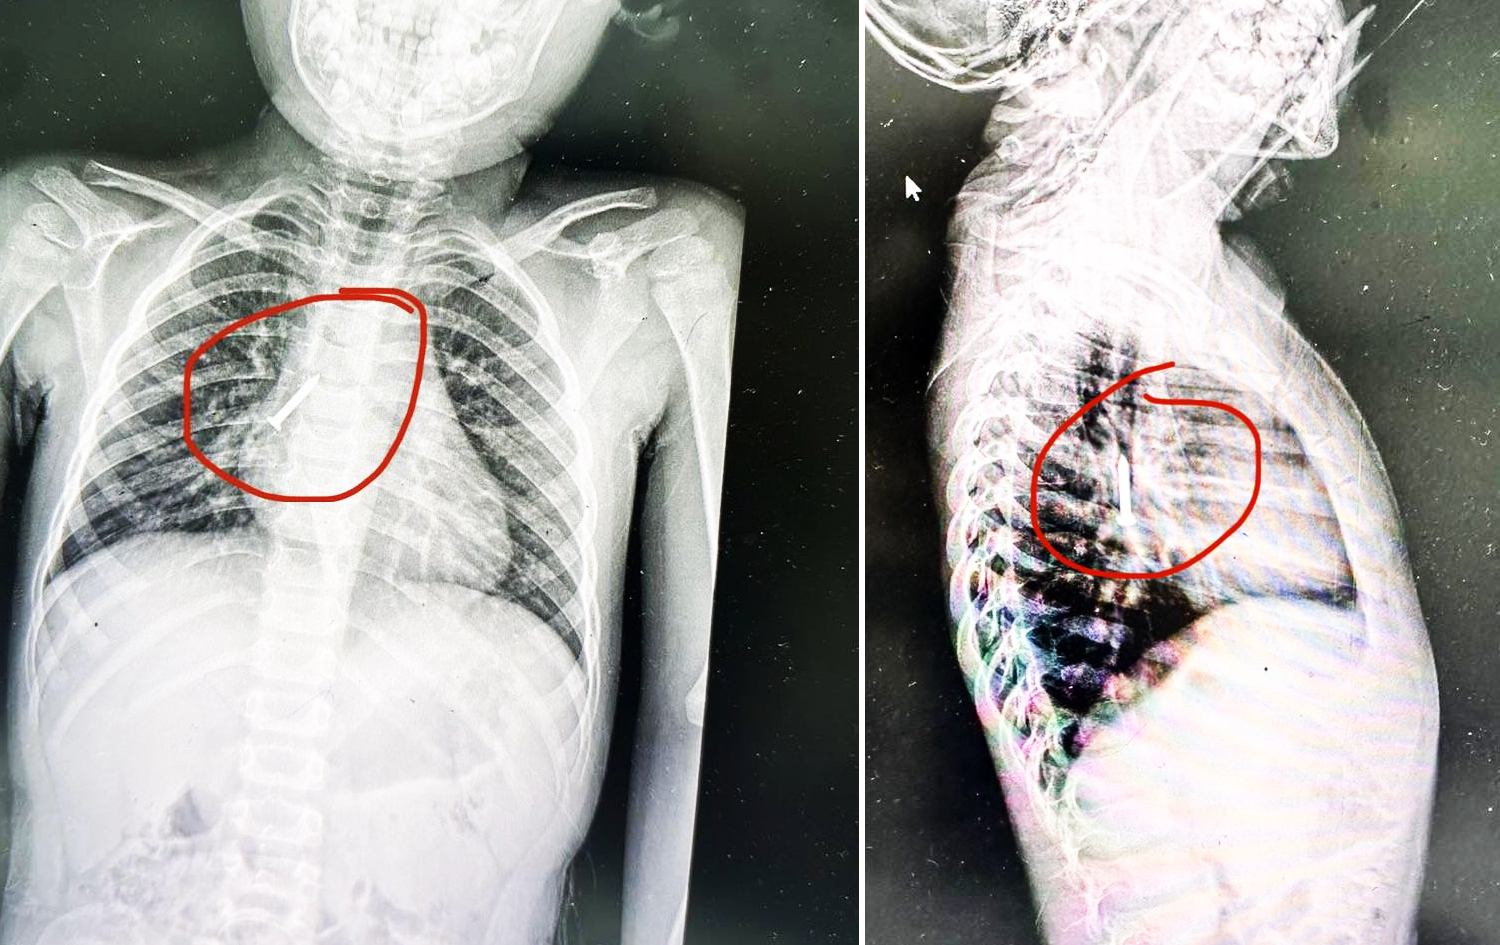

لە نەخۆشخانەی رزگاری لە هەولێر بزمارێک لەنێو بۆڕیی هەناسەی منداڵێک دەردەهێندرێت، ئەو پسپۆڕەی بزمارەکەی دەرهێناوە دەڵێت: زۆرجار منداڵ لە بێئاگاداییدا تەنی نامۆ دەخاتە نێو دەمی یاخود بە دەمییەوە دەیگرێت، ئەمەش لەو شێوەیە بووە.

ئەمڕۆ دووشەممە 4-8-2025 د. هێوران ئەنوەر، پسپۆڕی نەشتەرگەریی دڵ، سینگ و بۆرییەکانی خوێن بە رووداوی راگەیاند، ئەو بزمارە بۆڕیی هەناسەی سەرەکیی منداڵەکەی تێپەڕ کردبوو، بە هەناوبینیی رەق و بە سڕکردنی گشتی دەریان هێناوە.

دەرهێنانی ئەو بزمارە لە نەخۆشخانەی فریاکەوتنی رزگاریی فێرکاری لە هەولێر کراوە و بەپێی ئەو نەخۆشخانەیە، رۆژانە چەندان حاڵەتی لەم شێوەیە تۆمار دەکەن کە زۆرترینیان منداڵن.